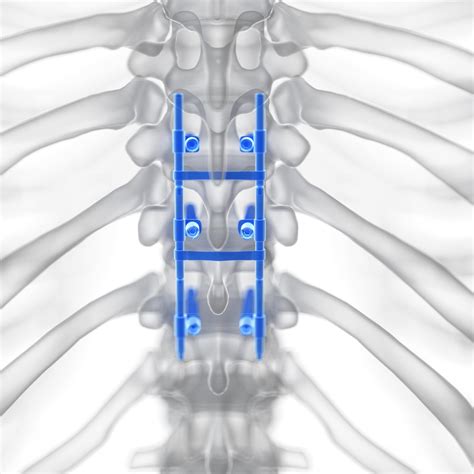

• Fixation: Plates, screws, or other fixation devices may be used to stabilize the vertebrae and promote fusion.